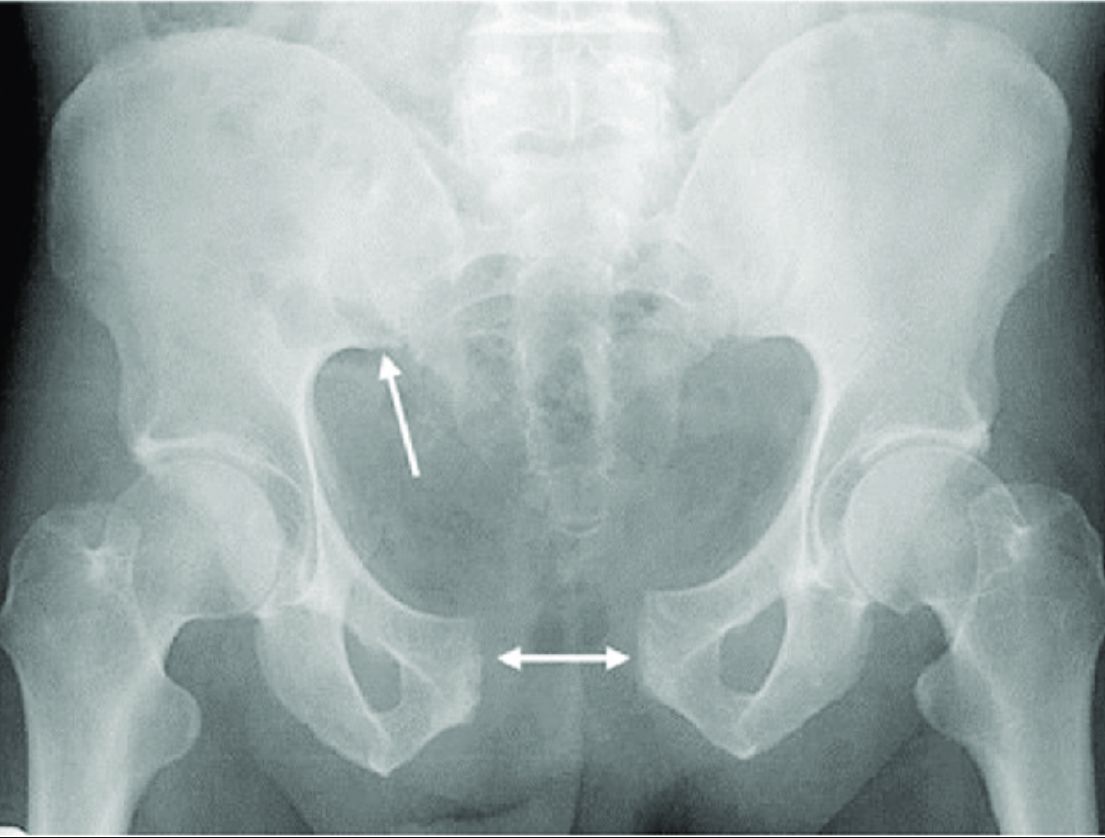

Рак лобковой кости симптомы лечение - фото презентация